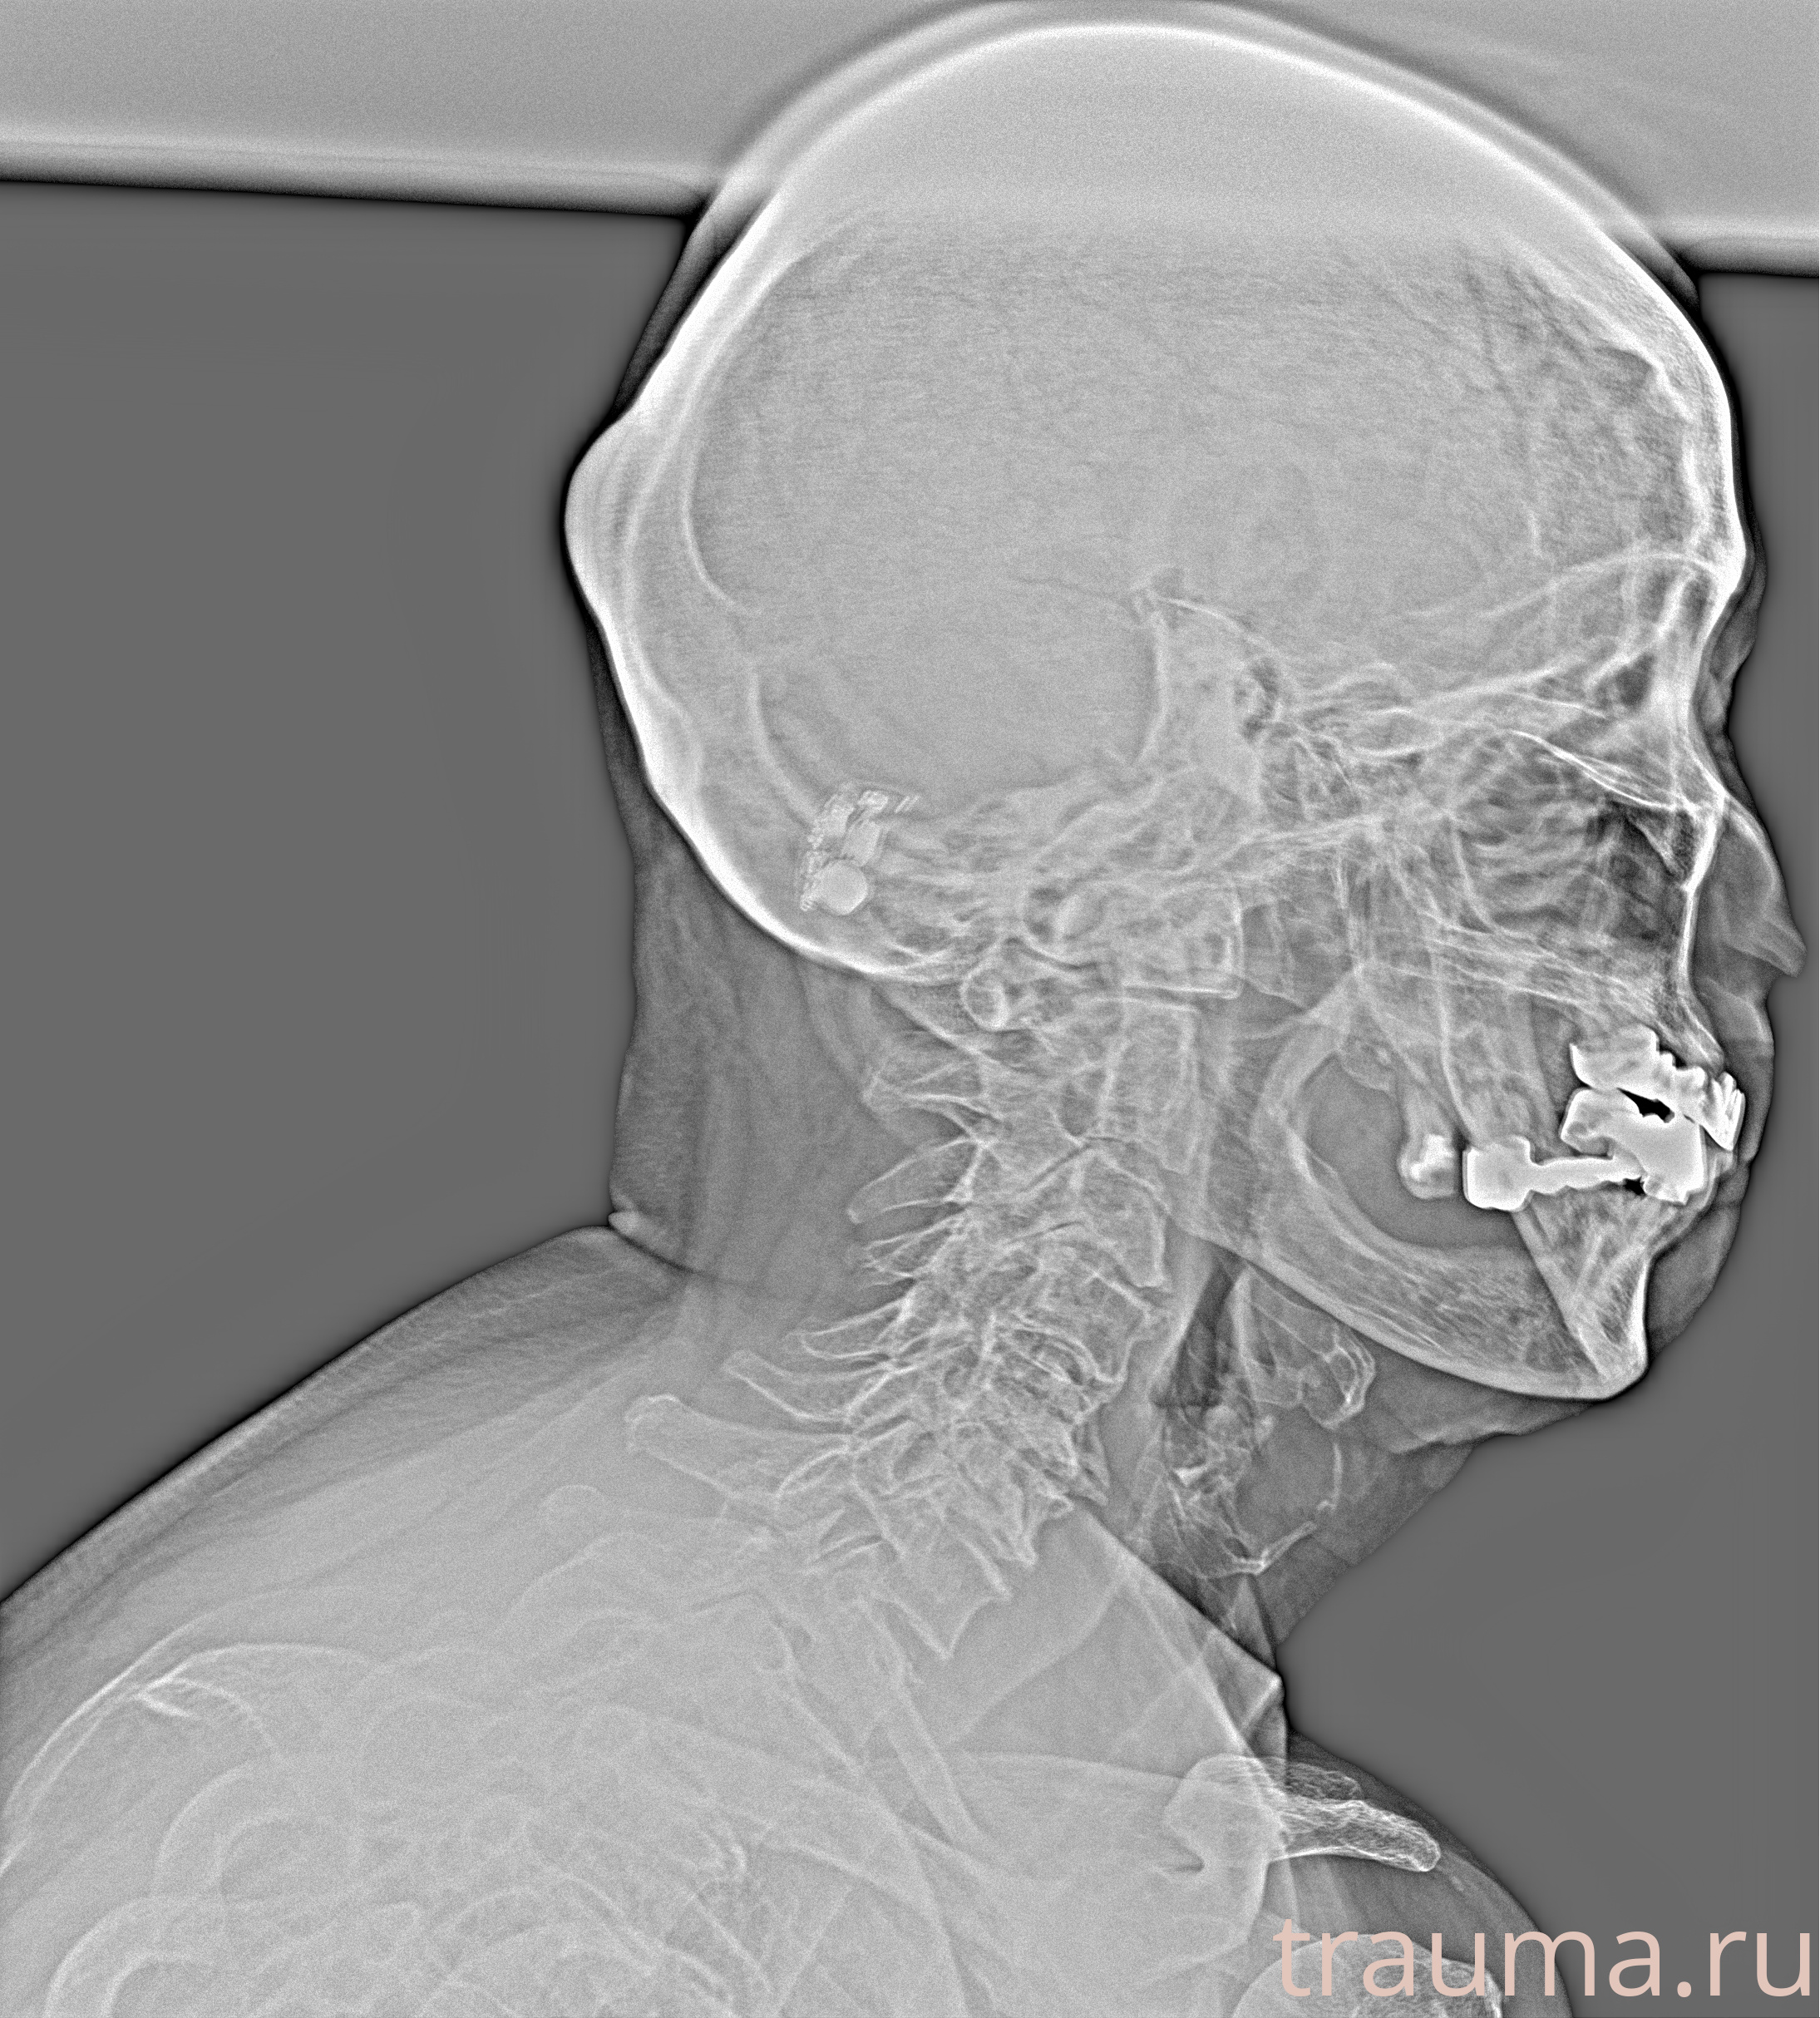

Рентгенограммы

Рентген на дому: по вашему адресу приезжает врач-рентгенолог, травматолог-ортопед с мобильным рентгеновским аппаратом, проводит диагностику травмы или заболевания, делает необходимые рентгенограммы, дает рекомендации по дальнейшему лечению. Получить качественные снимки в домашних условиях возможно благодаря уникальной методике, разработанной МосРентген Центром для института  Склифосовского